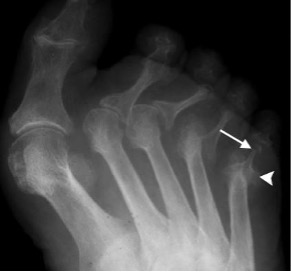

Sero-negative spondyloarthropathy

- Includes ankylosing spondylitis, psoriasis and Reiter’s syndrome; linked to HLA B27 antigen complexes

- Usually involves interphalangeal joints in an asymmetrical distribution

- Soft tissue swelling leads to dactylitis or ‘sausage digits’

- Loss of joint space and ill-defined erosions with proliferative new bone formation and periostitis

- Erosion of bone end into a sharpened pencil shape giving a ‘pencil in cup’ deformity

- Severe forms progress to ankylosis

Psoriatic arthropathy with new bone proliferation (arrowhead) and ‘pencil in cup’ appearance (arrow)